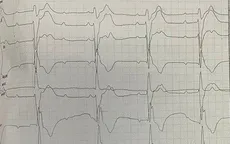

Nhập viện vì cơn nhịp tim nhanh, rối loạn nhịp tim tái phát

VTV.vn - Bệnh viện Đa khoa tỉnh Cao Bằng vừa tiếp nhận, xử lý kịp thời bệnh nhân có cơn nhịp nhanh kịch phát, rối loạn nhịp tim do chủ quan không đi khám và kiểm tra thường xuyên.